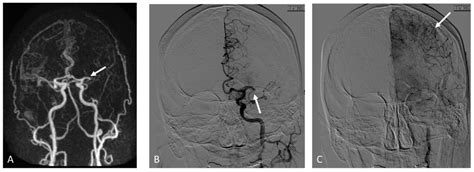

Case Study 3: MRI of the Brain